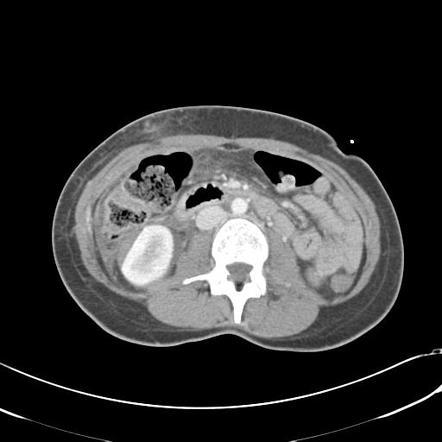

54m w/cirrhosis 2/2 alcohol

Arterial phase CECT w/multiple hyperdense/hypervascular foci c/w tumor (these wash out on PV phase where the tumor thrombus is also more apparent) we also see cirrhosis w/small nodular border

Criteria to distinguish portal vein tumor thrombus (vs. bland thrombus) are contiguity with parenchymal tumor, expansion of the lumen of the vein, and enhancing thrombus.